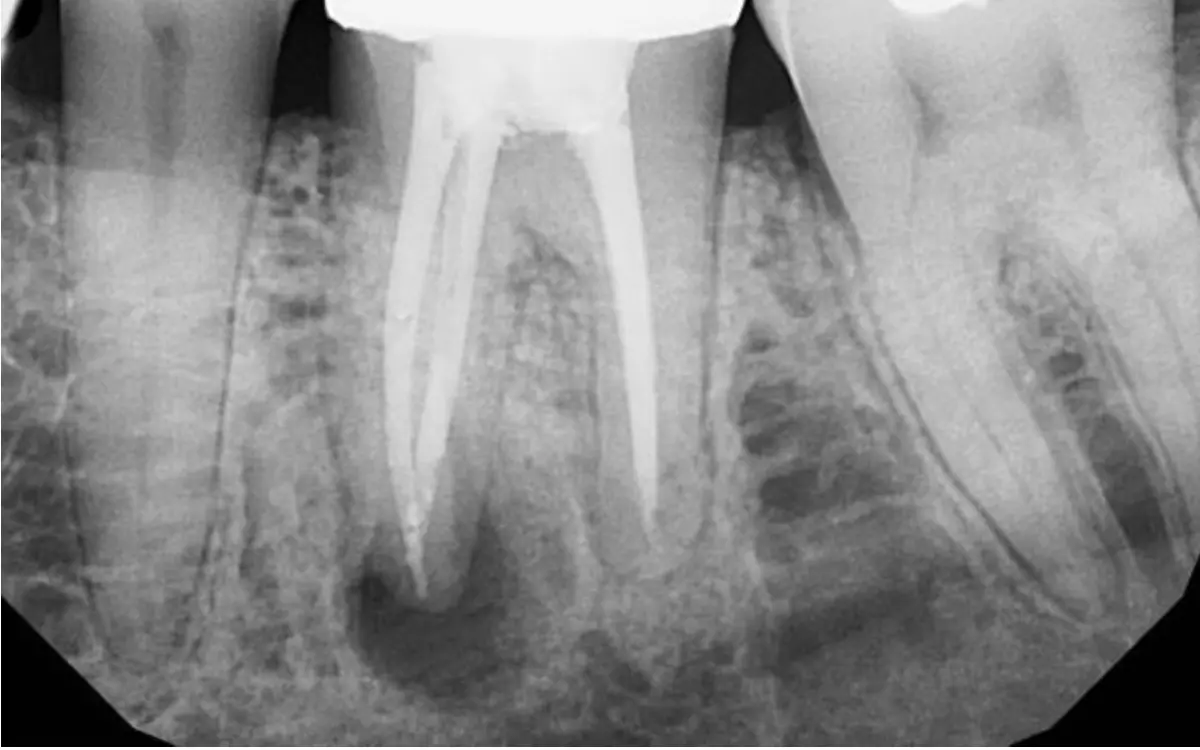

Круглый очаг поражения на верхушке зуба

Круглый очаг поражения на верхушке зуба — гранулема при периодонтите

• Выполняет прицельный снимок зуба. Хронические периодонтиты имеют яркую рентгенологическую картину. Снимок позволяет убедиться, что зачаток постоянного зуба не поврежден (если периодонтит в молочном зуба). Потом его фиксируют в истории болезни.